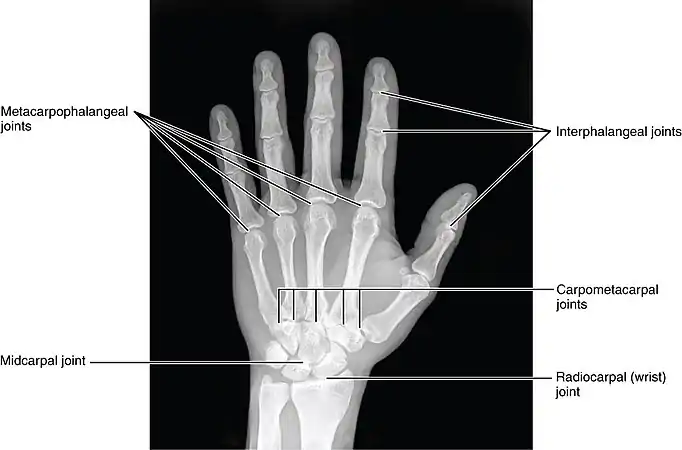

Unilateral extra phalangeal crease Joints of the hand in an X-ray image

Joints of the hand in an X-ray image Movement of the three finger phalanges; Distal, middle and proximal